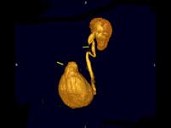

男,72岁,排尿困难1年余,无手术病史,CT扫描如图所示,下列说法正确的是?(?)

• A.一侧肾脏缺如

• B.膀胱的后上方可见一囊性肿物,该囊性肿物与膀胱相通

• C.考虑为先天性孤立肾

• D.该囊性肿物考虑为膀胱憩室

• E.该囊性肿物考虑为输尿管囊肿